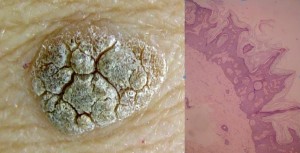

Acanthohyperkeratotic type of SK: the sharp projections adjoining the stratum corneum are called church spires

Ruguous surface are more evolutive SK with a histological diagnosis of Acanthohyperkeratotic type (AHCS). This corresponds to a thick stratum corneum.

Clinically smooth lesions were of the reticulate and/or acanthotic type and keratotic lesions were of the acanthohyperkeratotic type. If we consider that SK have pulsed stimulations to hyperproliferate or to accumulate, we can admit that all SKs evolve from paucicellular smooth lesions of the reticulate-acanthotic type to pluricellular thickened SK of the acantho-hyperkeratotic type. These paucicellular smooth lesions arise from macular SK, considered by some a solar lentigo. No clonal SKs were detected in our study and their probable rarity does not enable us to hypothesize a relationship between the clinical and histological picture of this subtype.